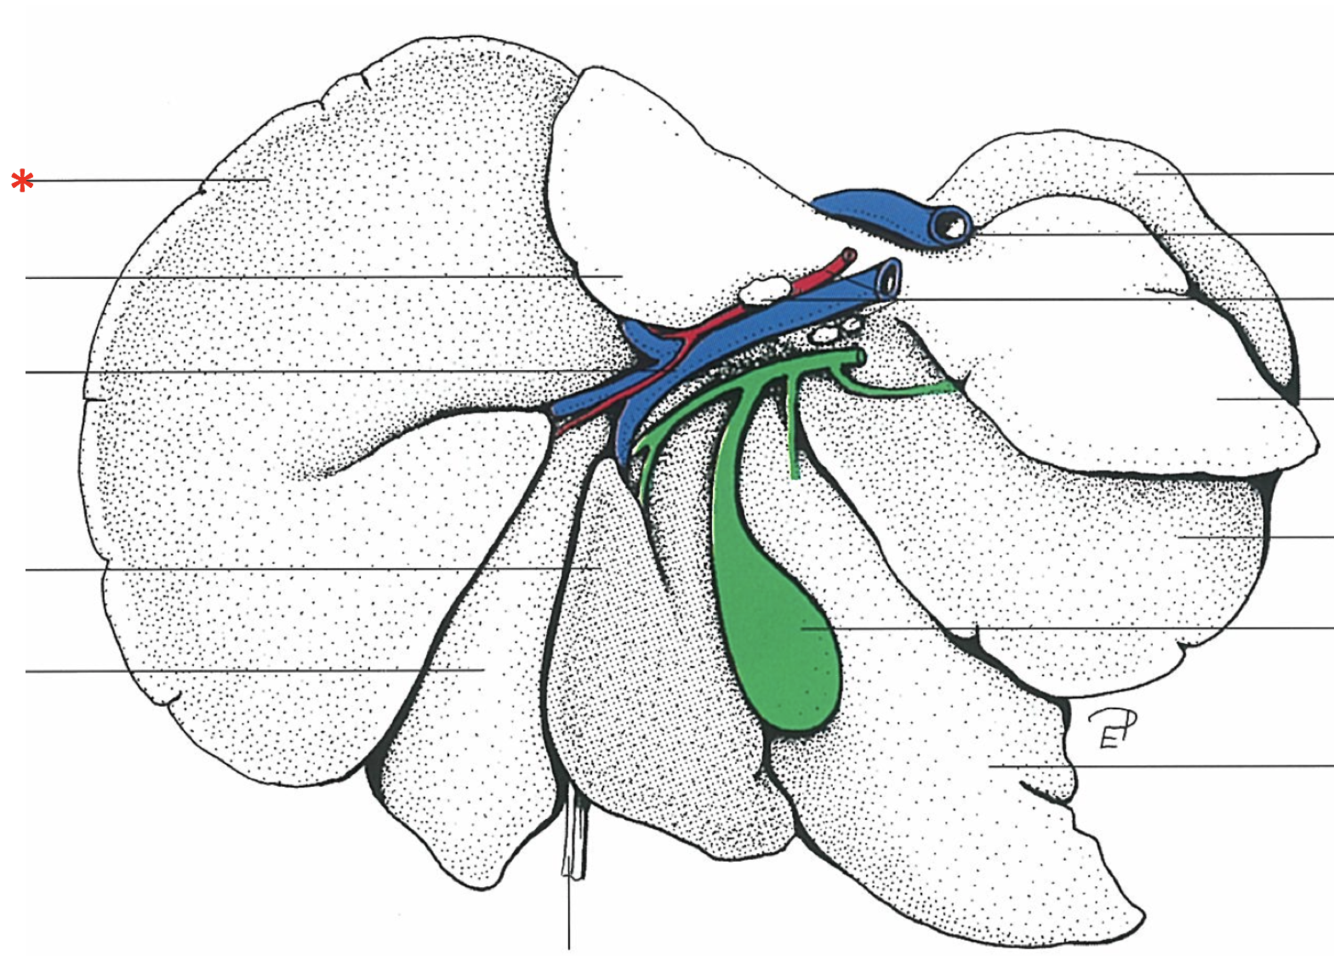

Porta hepatis

- With v. portae et a. hepatica

Lobus caudatus

Lobus quadratus

Lobus hepatis sinister medialis

Lobus hepatis dexter medialis

Lobus hepatis dexter lateralis

Proc. caudatus

V. portae

Proc. papillaris

Lobus hepatis sinister lateralis

Impressio renalis

Liver of a Cat

What is shown? Give the Aspect

Liver of a Cat

Fascies visceralis